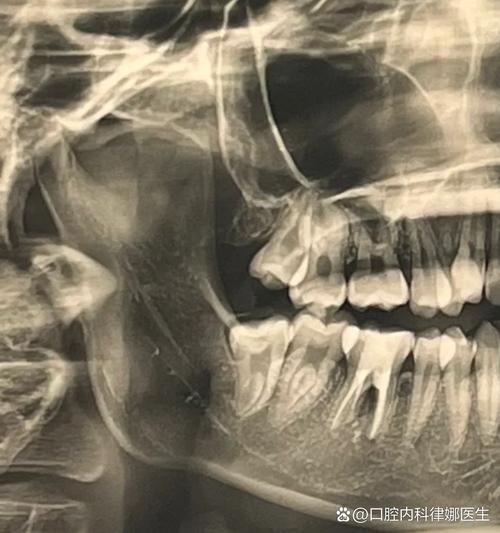

牙槽骨的骨高度、宽度、密度是决定能否植牙及选择何种种植体的核心指标,传统X光片(如根尖片、曲面断层片)是二维影像,存在放大失真、重叠干扰等问题,无法准确测量骨量,下颌骨后区的牙槽骨可能因吸收呈现“倒凹”形态,二维片容易误判骨量充足,实际三维CT才能清晰显示骨缺损区域,避免种植体穿出骨壁。

曲面断层片虽能显示全口牙槽骨,但影像重叠严重,无法区分骨皮质与骨松质,对神经、上颌窦等结构的定位误差可达2-3mm,下颌神经管实际距离牙槽嵴顶5mm,曲面断层片可能显示为7mm,若医生按此数据植入种植体,极易损伤神经,导致下唇麻木。 -